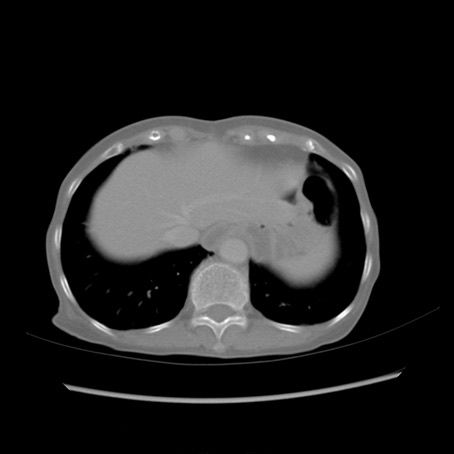

冠状断像

症例25(横断像)

【症例】80歳代女性

【主訴】胸のつかえ感

【現病歴】約9時間前に食後から胸のつかえた感じあり、嘔吐あり、来院。

【既往歴】胃癌(全摘)、胆摘、虫垂炎

【身体所見】心窩部に圧痛あり、反跳痛なし。

【データ】WBC 5700、CRP 0.05